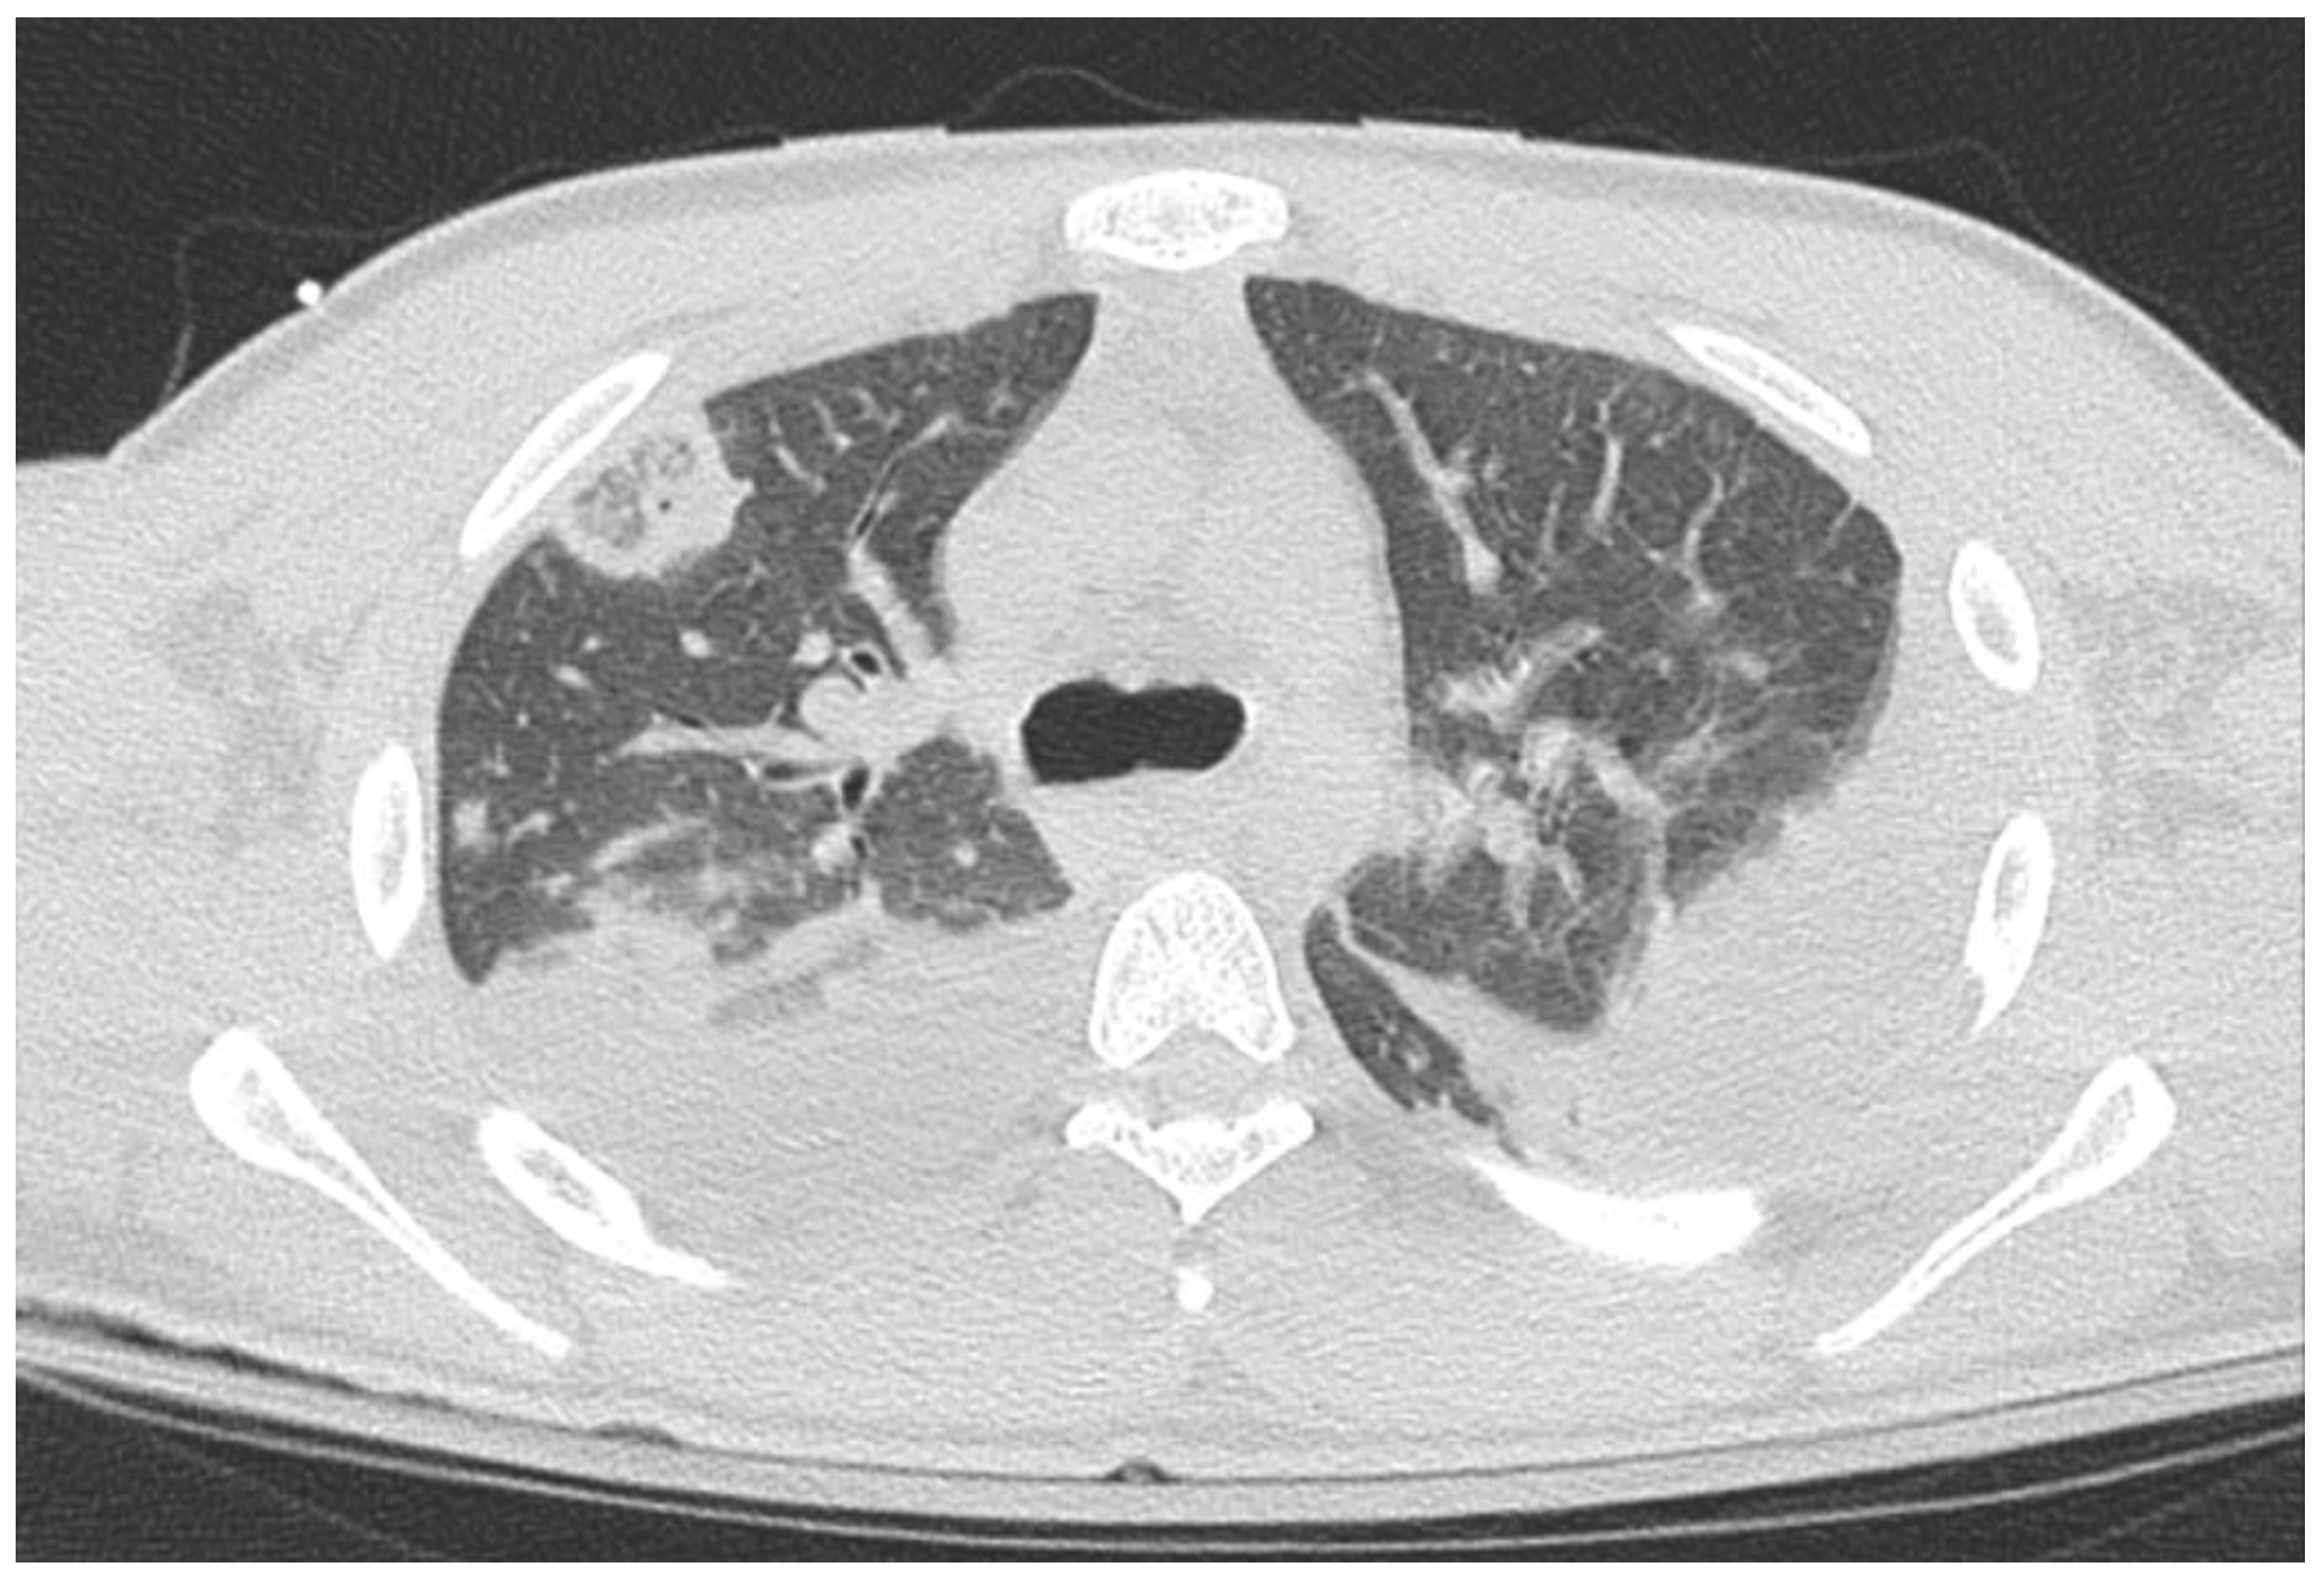

Case Presentation: